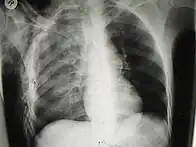

O enfisema pode produzir protuberâncias, como nódulos móveis com ruídos crepitantes a palpação. Em uma radiografia de tórax, o enfisema subcutâneo pode ser visto como estriações radioluzentes (escuras) nas áreas com músculos. O ar nos tecidos subcutâneos pode interferir na radiografia do tórax, potencialmente obscurecendo condições graves, como o pneumotórax. Também pode reduzir a eficácia do ultrassom.[8] Também é visível na tomografia e na ressonância magnética como bolhas escuras.